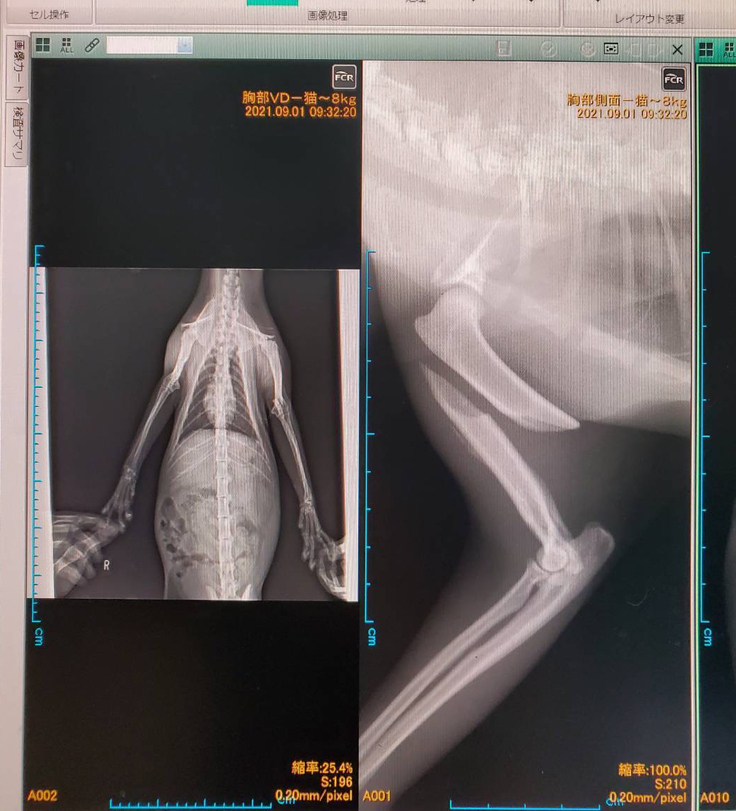

先住の地域猫のところへ2ヶ月ほど前から現れるようになったラッキー。

1週間ほど前にTNRを終え、夜いつものように餌をあげに行ったところ、右前足をぶらぶらさせて庇うように私の元へ歩いてきました。

顔にはいくつか傷も負っており骨折の疑いがある状態だったため、とても放っておくことができませんでした。

その日はそのまま自宅に連れて帰って保護し、次の日に病院へ連れていきました。

診察の結果、肩から肘の間の骨が折れており、獣医さん曰く、おそらく車にはねられたんだろうとの事でした。

また、獣医さんの話として、保護して自然完治を待つのも1つの方法ではあるが、骨のくっつき具合によっては足を引きずりながら生きていく事になるので、野良として生きるには苦労するだろうと言うことでした。